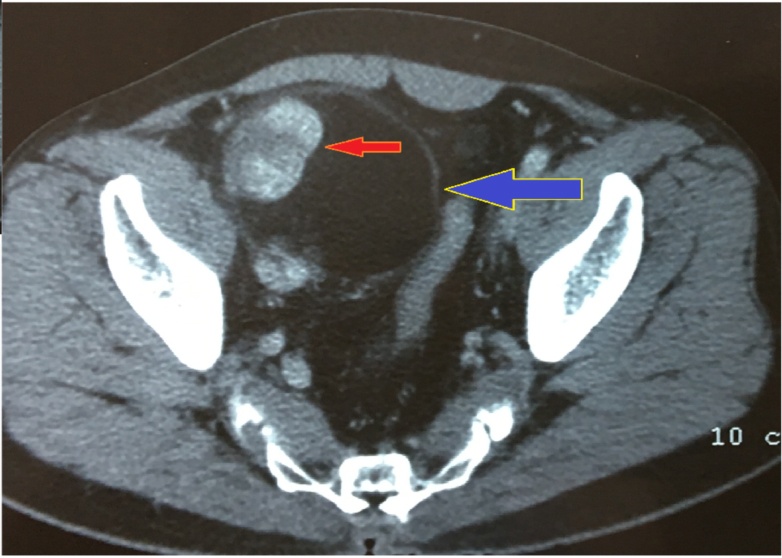

| Hình ảnh CT scan của bệnh nhân được các bác sĩ xem và đánh giá ngay trong phòng mổ . Ảnh: SYT cung cấp. |

Trước đó, các bác sĩ bệnh viện quận 9, TP.HCM tiếp nhận bệnh nhân 70 tuổi bị túi phình động mạch chậu chung bên phải, được chỉ định phẫu thuật cắt nối. Tuy nhiên bệnh nhân đang trên bàn mổ thì bất ngờ diễn biến xấu, đe dọa tính mạng.